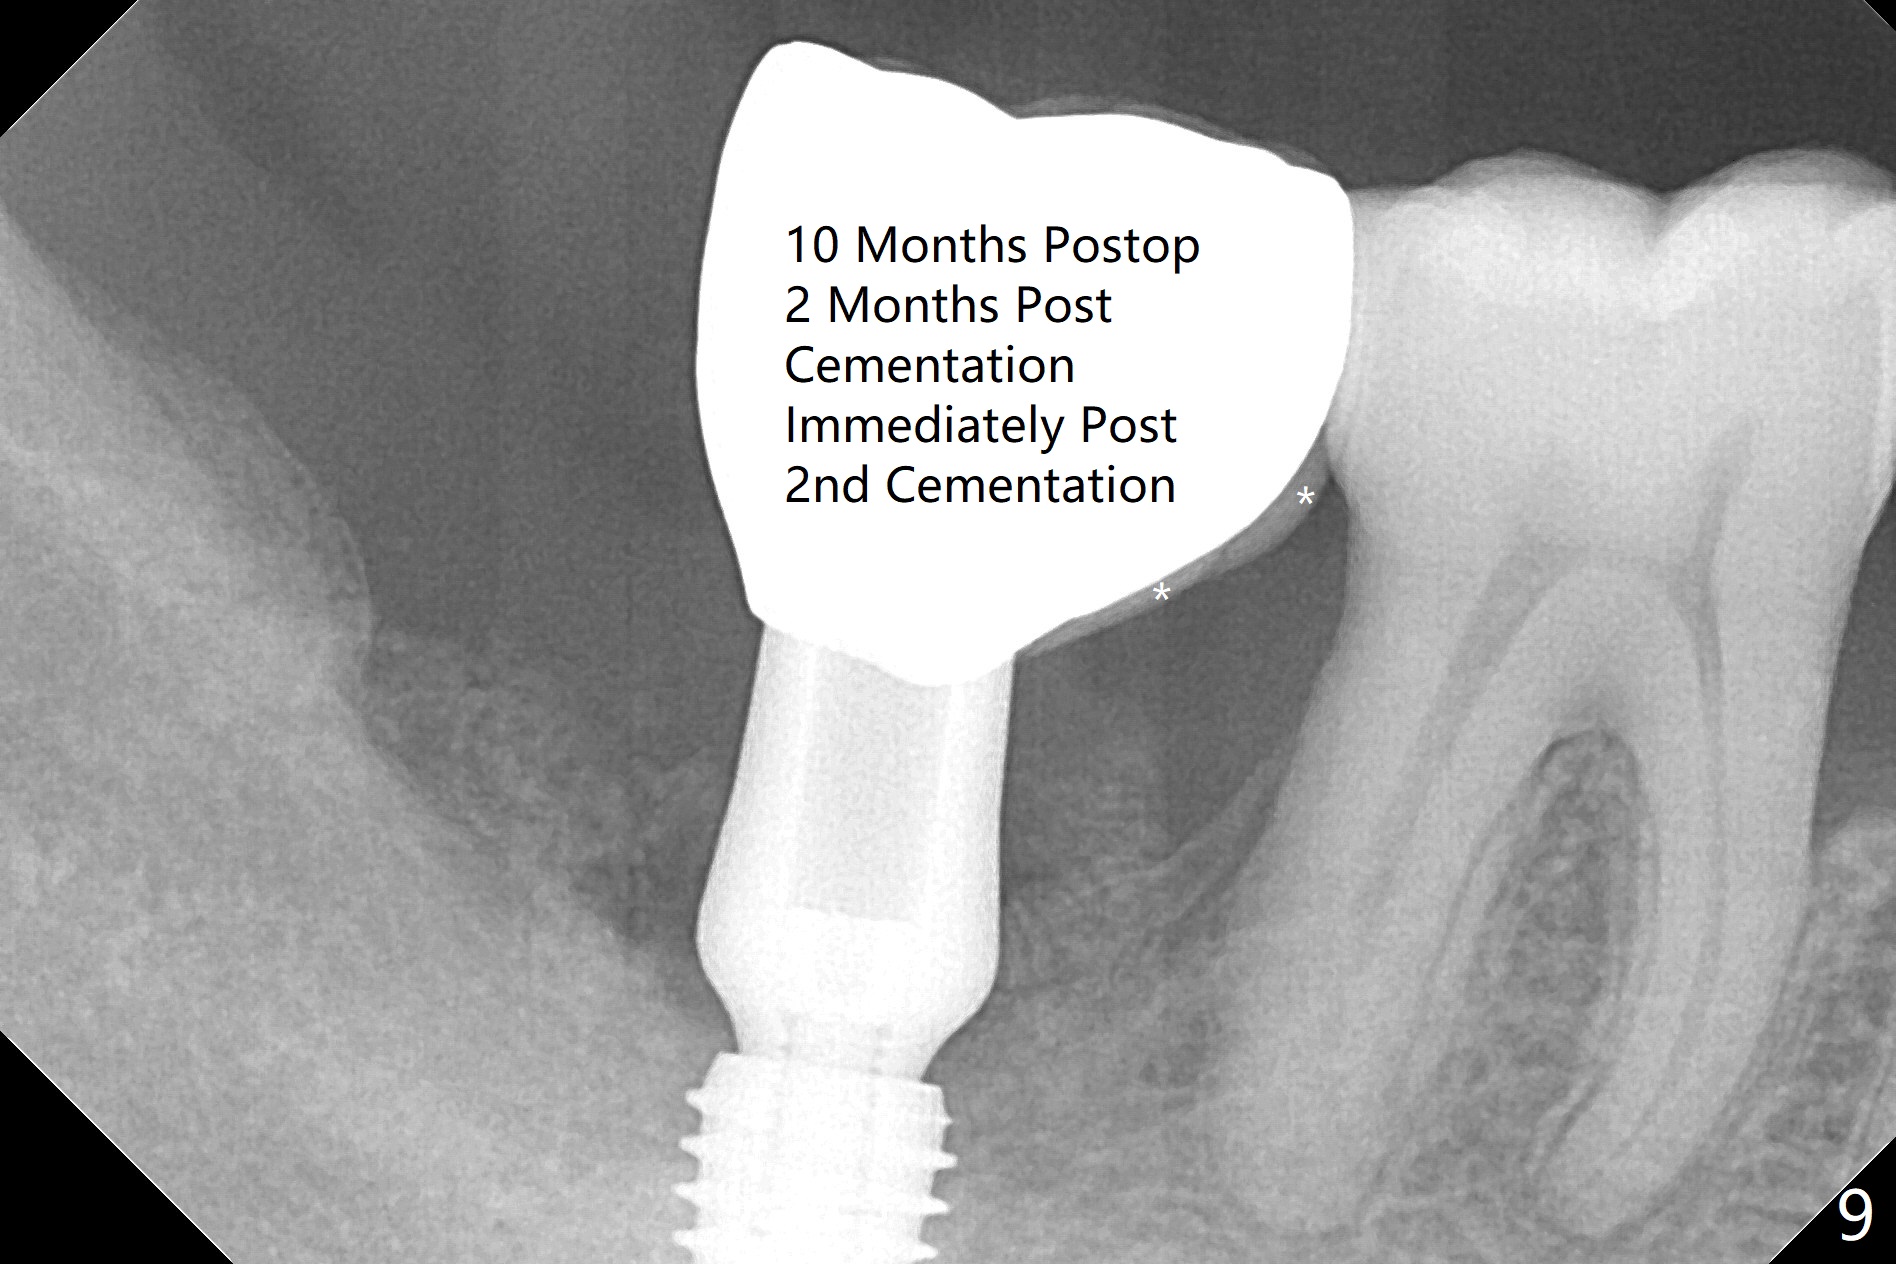

The affected tooth (#31, Fig.1) has severe buccal gingival recession with mobility III. After extraction and removal of granulation tissue, osteotomy is initiated in the middle of the fused socket using IS drills with 4 mm stopper (Fig.2,3). Following sequential osteotomy until 4 mm drill, a 4.5x10 mm IS dummy implant does not achieve primary stability, whereas 5x10 mm one does (Fig.4,5). Due to limited bone height confirmed intraoperatively, a shorter UF implant is placed with insertion torque 30 Ncm (Fig.6,7) with ~ 4.5 mm implant threads exposed coronally. After placing a 6.5x5(5) mm abutment, Vanilla Graft (*) and PRF membrane and collagen plug, an immediate provisional is fabricated to close the remaining socket. The tooth #32 is kept initially to increase the stability of the provisional and removed 8 day postop because of discomfort. A 5.5(2.5) mm mill abutment is changed to 3 months postop. The implant seems ready for impression 6 months postop (Fig.8). The bone graft remains around the apical portion of the mill abutment with apparently new bone formation around the coronal portion of the implant10 months postop (Fig.9); porcelain (*) has been added to close the mesial gingival embrasure and proximal contact gap. Due to unfavorable crown/implant ratio and poor trajectory, the crown/abutment becomes loose once post 1st cementation. Guided surgery would avoid the trajectory isssue.